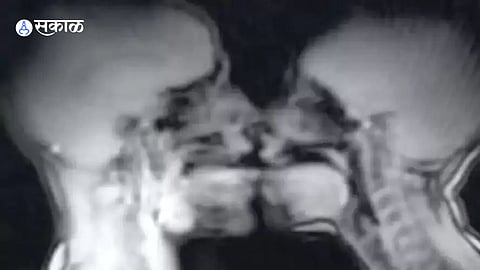

शारिरीक संबंधादरम्यान शरीरामध्ये काय काय बदल होत असतात या विषयावर शास्त्रज्ञांनी केलेल्या संशोधनाचा एक फोटो टीक टॉकवर व्हायरल होत आहे. खरं तर हे संशोधन काही वर्षापूर्वी केले होते. यासाठी वैज्ञानिकांनी MRI मशीनच्या आतमध्ये जोडप्याला शारिरीक संबंध करण्याच्या सूचना दिल्या होत्या. तो फोटो सध्या चांगलाच व्हायरल होत आहे.

हे संशोधन १९९१ ते १९९९ दरम्यान करण्यात आला होता. या संशोधनासाठी इडा सबेलिस आणि त्यांच्या प्रियकर असलेल्या जुप याने सहभाग घेतला होता. इडा यांच्या मित्राच्या सांगण्यावरून त्यांनी या संशोधनासाठी सहभाग घेतला होता असं सांगितलं आहे. शारिरीक संबंधादरम्यान महिलांच्या शरिरीत होणारे बदल या संशोधनातून समोर आणण्याचा प्रयत्न केला गेला.

एम्स्टर्डम येथील Vrije University मध्ये हे संशोधन पार पडले असून इडा हिने सांगितलं की त्यांनी स्पूनिंग पोझिशनमध्ये सेक्स केला होता. तर या संशोधनातून महिलांचा प्रायव्हेट पार्टचे छिद्र हे सरळ नाही हा खुलासा झाला. अनेक वर्षापासून महिलांचा प्रायव्हेट पार्टचे छिद्र हे सरळ असल्याच्या चर्चा होत्या. १९४२ मधील लिओनार्डो द व्हीन्सी यांच्या एका पेंटिंगमध्ये महिलांच्या प्रायव्हेट पार्टला सिलेंडर सारखं दाखवण्यात आलं होतं.

या संशोधनात अनेक जोडप्यांनी भाग घेतला होता. त्यावेळच्या या संशोधनातून अनेक लैंगिक खुलासे झाले होते.